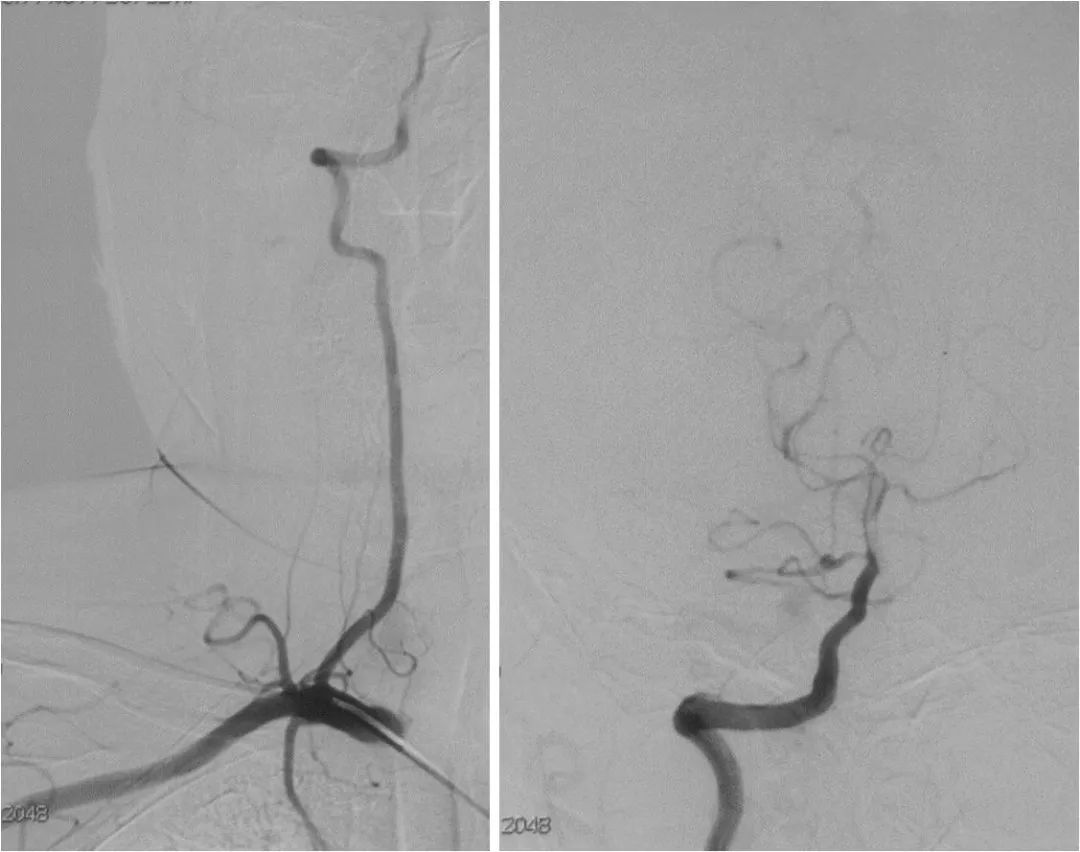

DSA:右大脑中动脉M1段重度狭窄,后循环向前循环代偿欠佳(图7-10)。

图7

图8

图9

图10